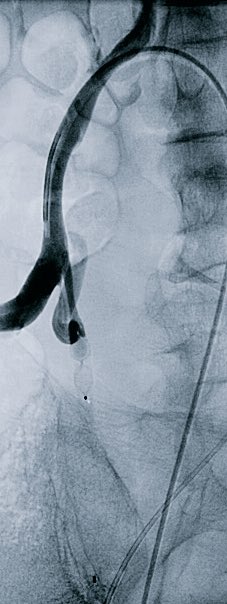

72 yo w/acute urinary retention 2/2 BPH. Remote h/o TURP. VIR consulted for PAE. Great clinical result. For more case info check out AlbanyIR.com/pae-case-1 and AlbanyIR.com/prostate-arter… for more about PAE. #IRad #PAE SIR RFS JVIR

72 yo w/acute urinary retention 2/2 BPH. Remote h/o TURP. VIR consulted for PAE. Great clinical result. For more case info check out AlbanyIR.com/pae-case-1 and AlbanyIR.com/prostate-arter… for more about PAE. #IRad #PAE <a href="/SIRRFS/">SIR RFS</a> <a href="/JVIRmedia/">JVIR</a>